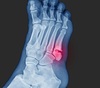

4

9